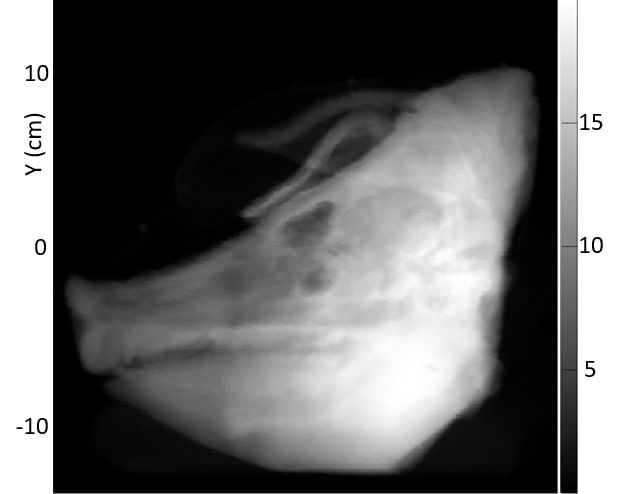

3.B. Comparison of acquired pRad with simulated pRad DRR

Fig. 4 shows the acquired pRad WET image of the pig’s head, along with the simulated pRad DRR from the x-ray CT with the corresponding difference image, and a simulated pRad DRR from the pCT with the corresponding difference image. Relatively large differences around the edges of the head and other areas of rapid variation occur because they are sensitive to a precise alignment of the two images. The four CT markers are visible in the x-ray CT difference image (Figure 4 middle row) at coordinates near (-9,1), (3,0), (3,9), and (11,10) cm. These markers have high x-ray attenuation but do not have a correspondingly high RSP. They are well-aligned in the difference image and appear with net negative WET values since x-ray CT overestimates the RSP of the marker materials. In the case of the pCT difference image (Figure 4 bottom row), the marker RSPs are identical, and therefore the markers are not visible. The slight difference of about 1 mm observed in the air around the pig’s head is likely due to a calibration issue for the 120 MeV protons that travelled deep inside the scintillator. There is a faint grid structure visible in the background of the x-ray CT difference image; this is an artifact due to non-uniformities in the construction of the tracking plane. We are currently upgrading the system, and expect to correct these non-uniformities in the next version.

Most soft-tissue regions of the head, including the brain and head and neck muscles, show agreement within 1-2 mm of WET between the acquired pRad and simulated pRad DRR, 1% in comparison to a total WET of up to 200 mm. The most notable anatomical WET differences are in the sinus region and the tympanic bullae, where the measured WET from the real pRad is 4 to 8 mm lower than the WET from the simulated pRad DRR. The sinus result is similar to that reported for a pig’s head in Deffet et al. 8; however their range-probe image did not contain the tympanic bullae. These large differences do not appear in the simulated DRR from pCT. There are smaller discrepancies in bony regions including the skull and mandible.